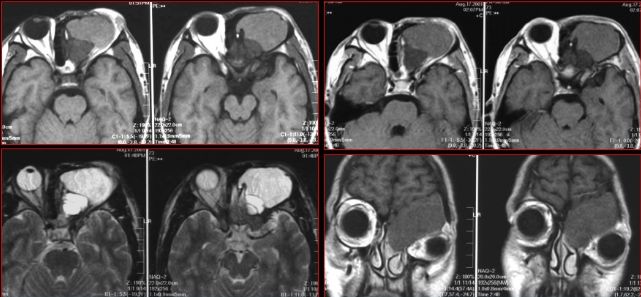

慢性多发鼻窦炎—MRI

鼻窦炎—骨质改变